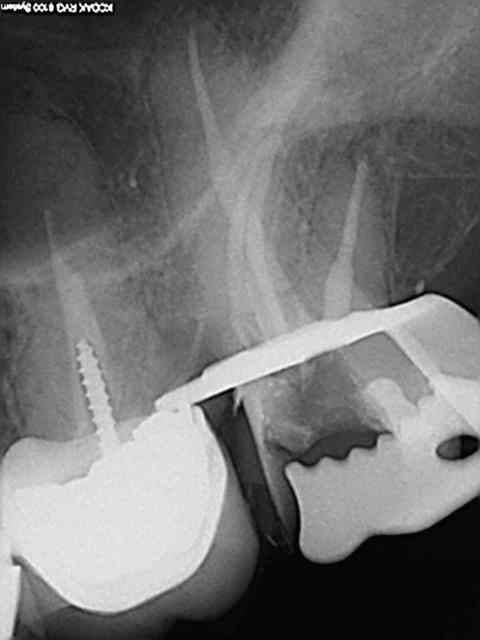

Exemple concret, de ce samedi (exceptionnellement au boulot car c'est un pote qui travaille sur Paris et qui a une semaine de vacances), j'en ai tous les jours.

la première radio date de 2011 issue d'un status inutile selon la sécu. Suspicion de reprise en mésial sous l'onlay de 27, noté sur le dossier à surveiller. Le patient appelle pour douleurs lancinantes spontanées la semaine dernière en haut au fond et à gauche exacerbées par le froid.

Diagnostic clair net et précis et par téléphone en plus : ca n'est pas du au tt merdique de la 26. Ce qui est confirmé in situ par la radio numéro 2 prise le jour meme de l'endo.

Comme à mon habitude je m'excuse d'avoir irradié le patient copieusement ( à raison de 70 kv et 0,099 s par cliché) plutot qu'un seul cliché argentique en fin de tt ( 70 kv aussi mais 1,3 s d'exposition lui) développé en fin de journée comme ca a du etre le cas pour le tt de 26 ( et m... encore raté).

Je sais pas moi mais le résultat parle de lui meme ( putain de mv2 que j'ai réussi à choper dans un 2 eme temps une fois les autres obturés)

Taille empreinte provisoire dans la foulée , l'avantage de la gutta chaude.

Vous préférez quoi dans votre bouche ? une seule radio et un tt endo comme la 26 ou 6 clichés et mon tt endo de 27 ?